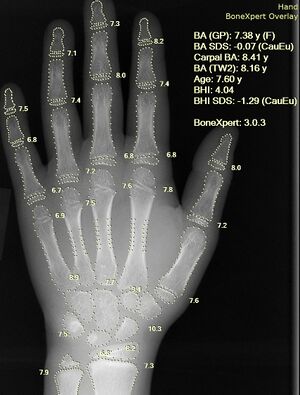

Применение искусственного интеллекта в медицине сравнительно ново, исследования в этой области продолжаются и охватывают различные медицинские специальности и смежные отрасли. ИИ применяется в задачах диагностики, разработки протоколов лечения[4], разработки новых препаратов, персонализированной медицины[5], мониторинга пациентов и организации ухода[6]. Особое значение имеет потенциал ИИ в обработке и интерпретации рентгеновских снимков, как наиболее часто выполняемых исследований в радиологии[7].

- Глубокое обучение и свёрточные нейронные сети — для анализа изображений (рентгенограммы, КТ, МРТ, фотографии кожных заболеваний)[23].